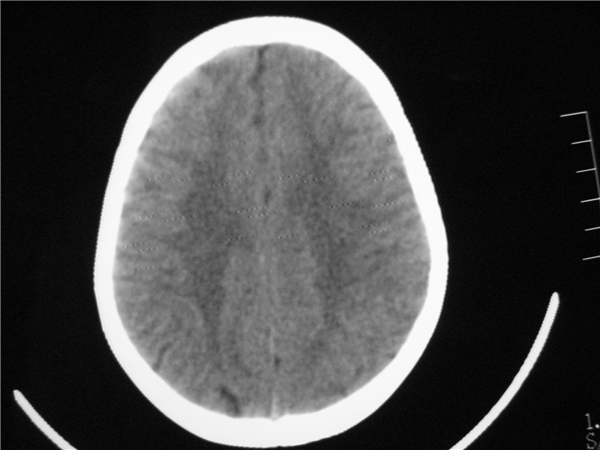

标题: PED2843: CT-23675 F 4Y 大家看看颅内有问题没。 [打印本页]

标题: PED2843: CT-23675 F 4Y 大家看看颅内有问题没。

四脑室扩大,三脑室稍扩大上移

胼胝体发育不全??

四脑室扩大,,六脑室

四脑室扩大,密度降低,图像的问题?建议mr扫描。